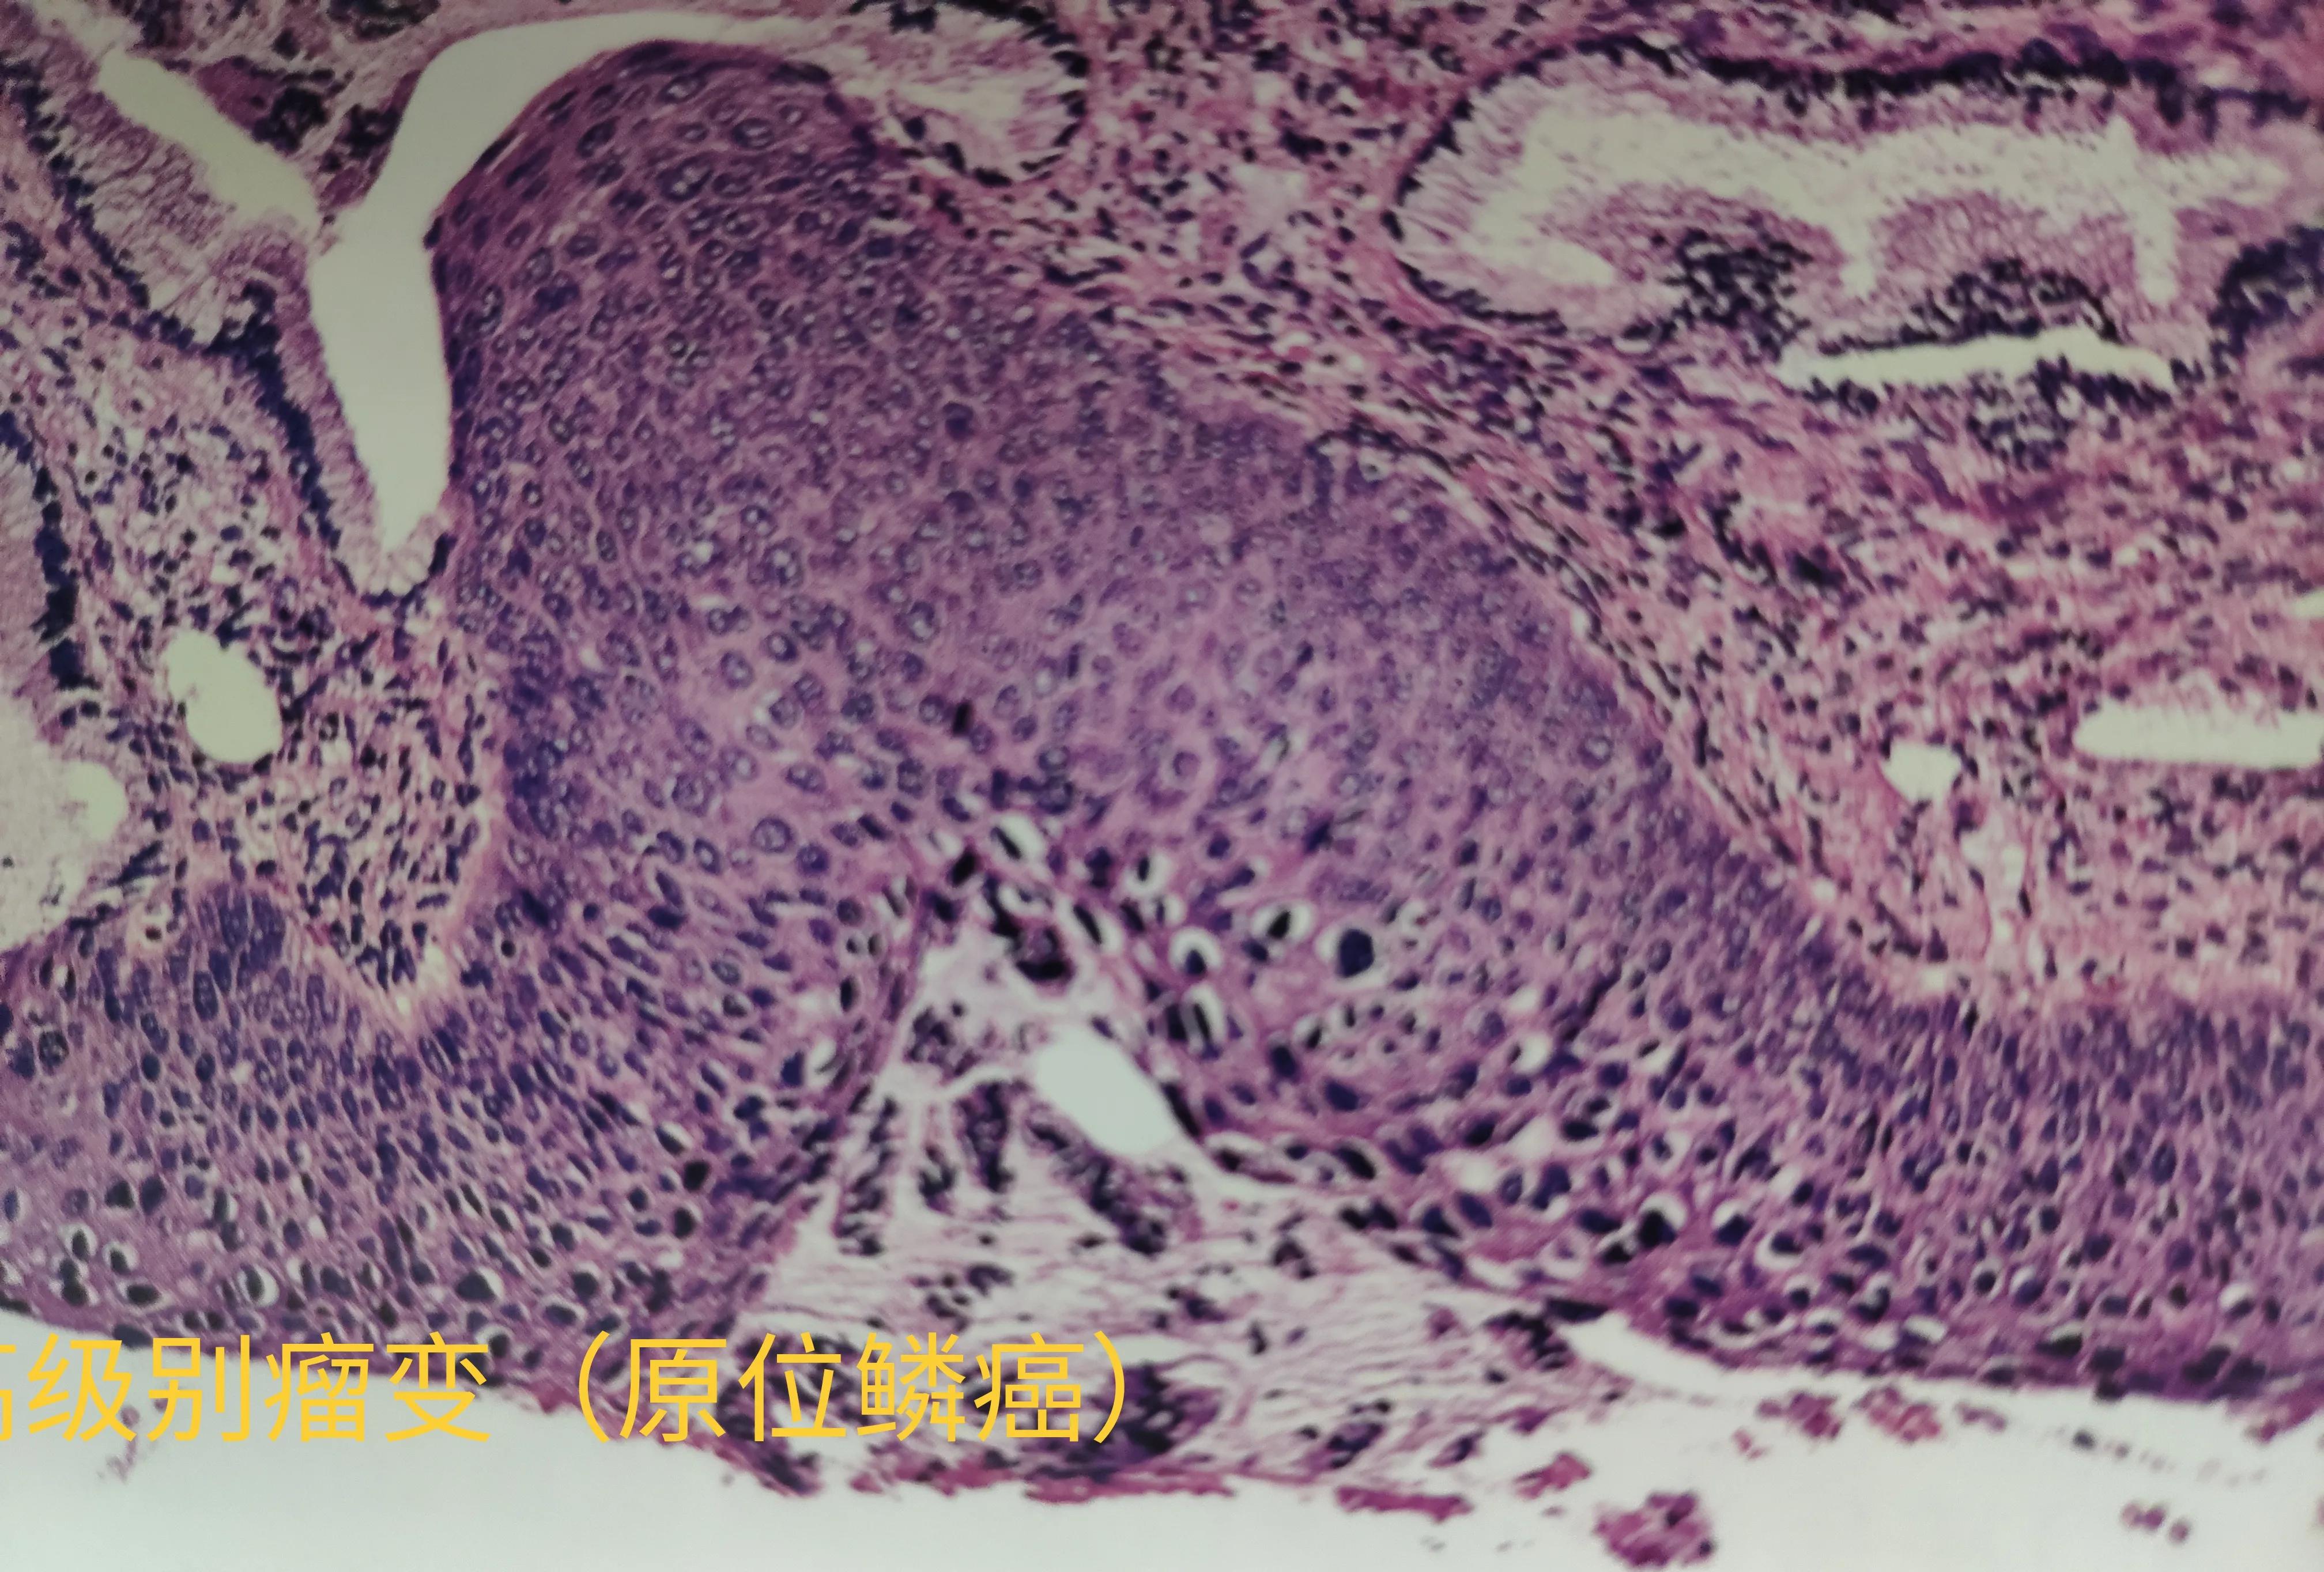

皮肤原位鳞癌

各型上皮均附着在底部的一层纤维膜上,这层膜叫基底膜。当癌变细胞局限于表面或腺腔内,没有破坏、突破基底膜时,就说癌仍然在原有位置上,所以称原位癌。

理论上讲,原位癌是各型癌产生、发展的必须经历的早期阶段,由于原位提供细胞生长所需的养份有限,癌细胞生长缓慢,有些癌可以长期处于原位状态而不再进展,或者进展缓慢甚至达到数年之久,可癌细胞能够产生一些组织酶,不断地降解破坏基底膜,终于有一天突破了基底膜,进入间质,就是常说的发生了浸润,进入了快速生长模式。

理论上讲,因为原位癌细胞没有进入基底膜外间质,也就不会发生淋巴道和血道转移,同样也极少会引起免疫系统的反应。在此阶段,只要完整切除原位癌病灶就足够了。